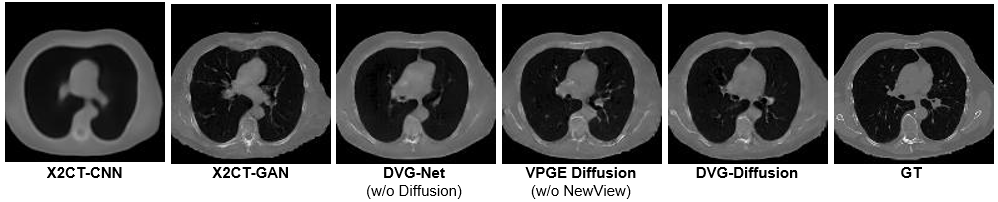

A similar challenge persists when applying diffusion models. Based on our proposed framework, we constructed three models for comparison: (1) DVG-Net model, which uses a CNN-based method (novel view generation stage) for reconstruction; (2) VPGE-Diffusion model, which employs a diffusion-based approach without additional synthesized views for guidance during our diffusion generation stage; and (3) our complete DVG-Diffusion model. As shown in Table VII, all three models outperform the X2CT series, benefiting from our proposed VPGE, which constructs an aligned latent space that reduces the difficulty of 2D-3D learning. However, purely diffusion-based VPGE-Diffusion model shows better perceptual metrics (LPIPS decreased from 29.50 to 28.11) but worse fidelity (SSIM decreased from 0.702 to 0.667) compared to the CNN-based DVG-Net. In contrast, our DVG-Diffusion model achieves a superior balance between these two aspects, maintaining high fidelity while significantly improving perceptual performance. This observation is further supported by Fig. 8, where the VPGE-Diffusion model produces CT volumes with higher visual quality but noticeable structural distortions, while the DVG-Net model reconstructs structures more accurately but suffers from over-smoothed details. Our proposed DVG-Diffusion model effectively combines the strengths of both approaches, delivering superior performance in both image detail and structural integrity. This is attributed to the use of additional new views for guidance in DVG-Diffusion, which are derived from the DVG-Net model’s superior structural information. By leveraging these high-quality structural features as guidance, DVG-Diffusion ensures precise CT volume reconstruction without compromising the inherent generative capabilities of the diffusion process.

TABLE VII: Performance comparison of CT reconstruction between CNN methods and generative methods (GAN,Diffusion).

View Model PSNR \uparrow SSIM \uparrow LPIPS \downarrow

Single X2CT-CNN [13] 22.18 0.553 44.27

X2CT-GAN [13] 21.40 0.505 39.62

DVG-Net (Ours) 23.08 0.568 38.59

VPGE-Diffusion (Ours) 22.29 0.532 37.59

DVG-Diffusion (Ours) 22.54 0.541 36.79

Biplanar X2CT-CNN [13] 26.34 0.682 37.29

X2CT-GAN [13] 24.82 0.613 31.73

DVG-Net (Ours) 27.25 0.702 29.50

VPGE-Diffusion (Ours) 26.47 0.667 28.11

DVG-Diffusion (Ours) 26.84 0.679 27.35